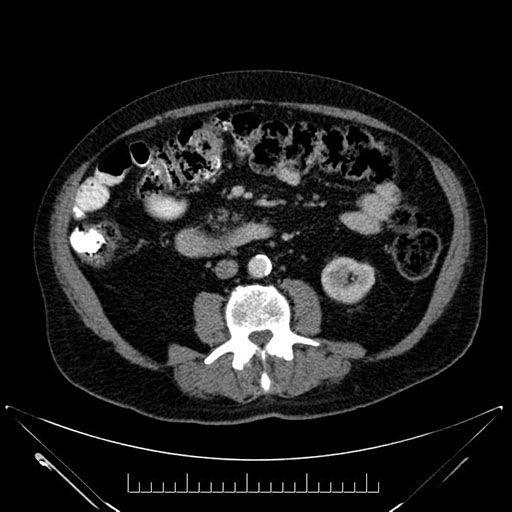

Imaging Analysis

Look through the patient's CT scan to identify any areas of concern for the necessary procedure.

Based on your CT findings, which issue(s) would give reason for "planned slowing down moment(s)" in this case?

Considering a standard Whipple procedure, what step(s) of the operation would you do differently in this case?